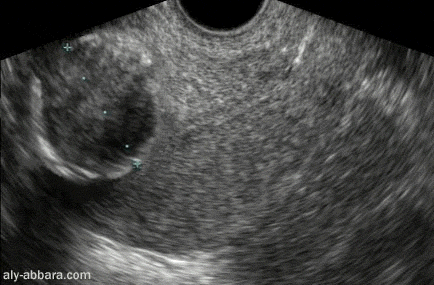

Fibrome utérin intra-mural calcifié

de 35 x 25 mm de diamètre

Coupe sagittale de l'utérus par voie endovaginale

On peut distinguer sur cette image

échographique les dépôts du calcium

sur la surface du fibrome qui prennent un aspect dense hyperéchogène